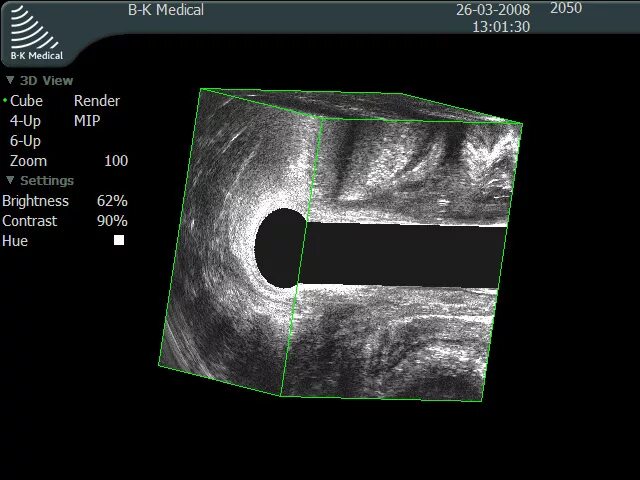

Узи кишечника как подготовиться